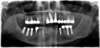

2 implants coniques en bas à droite, parallèles entre eux, et parallèles à l’axe des dents voisines, avec leur vis de cicatrisation, remplaçant les racines des 2 premières molaires

3 implants coniques en bas à gauche, parallèles entre eux, et parallèles à l’axe des dents voisines, avec leur vis de cicatrisation, remplaçant les racines des 2 premières molaires

2 implants coniques en haut à gauche, parallèles entre eux, et parallèles à l’axe des dents voisines, avec leur vis de cicatrisation, remplaçant les racines des 2 premières molaires, dans l’alignement des dents antagonistes